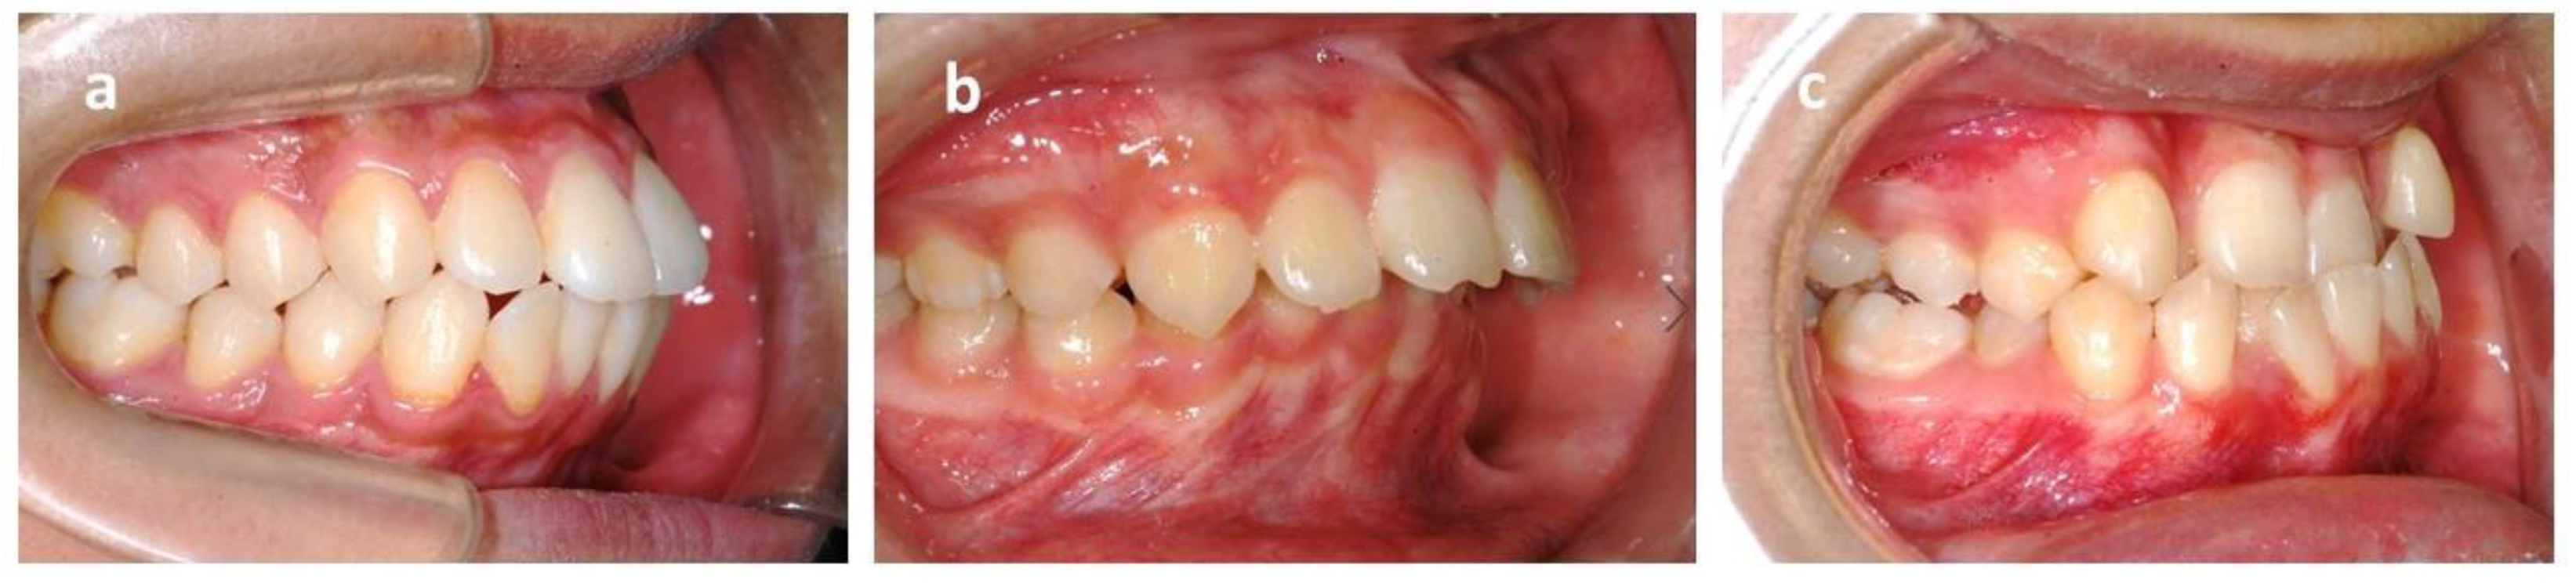

ICON is an index of complexity outcome and need that is used for assessing the orthodontic treatment need (Figure 4). ICON has been proposed as a multipurpose occlusal index, including dental components such as crowding measured with the irregularity index/spacing (sagittal dimension), cross bites (transverse dimension), anterior open bite/overbite (vertical dimension), and sagittal posterior occlusion relationship as well as the esthetic component. The esthetic component comprised 10 color photographs showing dentition in the frontal view graded from 1 (most attractive) to 10 (least attractive). The dental indices were documented as numeric values according to the standard. The final ICON score was divided into malocclusion complexity grades (<29 = easy, 29–50 = mild; 51–63 = moderate, 64–77 = difficult, >77 = very difficult). A cutoff point of 43 was set to mark a definite need for orthodontic treatment [41].

Figure 4. Dental component scale of index of complexity outcome and need (ICON). (a) Crowding: crowding occurs when there is a discrepancy between the space required by teeth and the space available in the jawbone. The irregularity index is used for measurement. (b) Spacing: the opposite of crowding, the space available is larger than space required. (c) Posterior buccal crossbite: buccal cusp of the mandibular dentition occludes lingually to the lingual cusp of the maxillary dentition. (d) Posterior lingual crossbite: buccal cusp of the mandibular dentition occludes buccally to the buccal cusp of the maxillary dentition. (e) Anterior crossbite: maxillary incisors occlude lingually to mandibular incisors. (f) Open bite: there is no vertical overlap between the maxillary and mandibular incisors. (g) Overbite: the vertical overlap of the incisors.